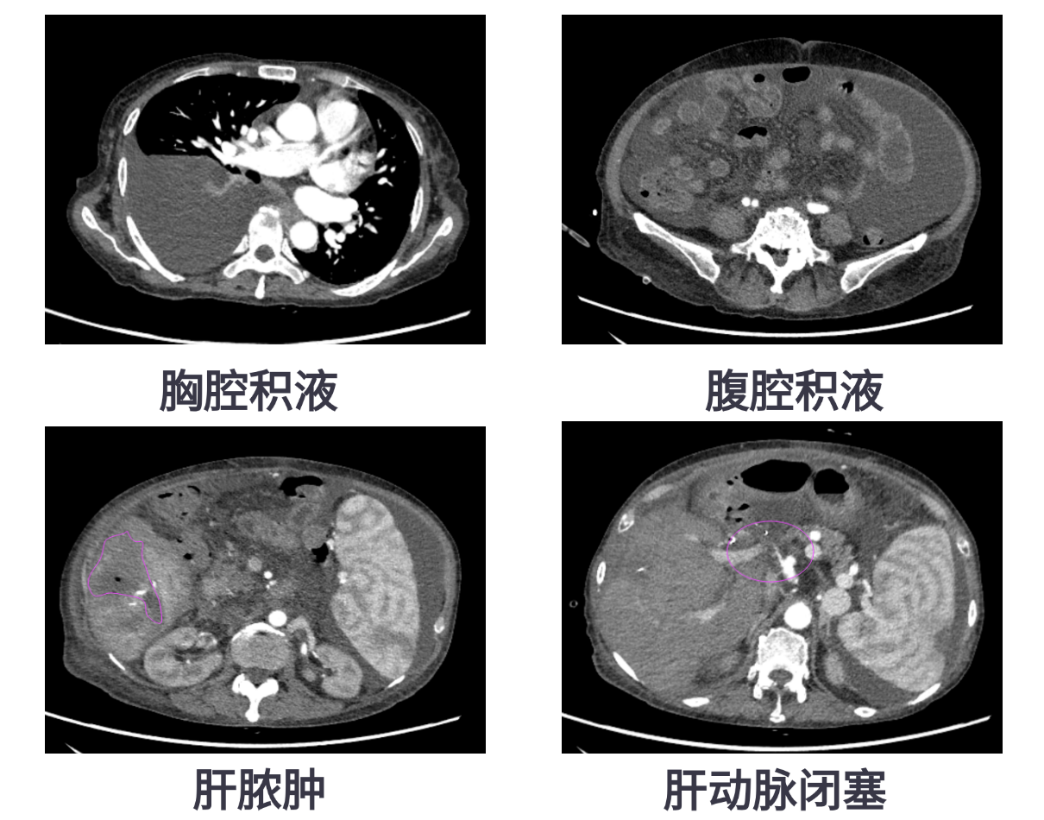

肝移植是治疗终末期肝病的重要手段,但术后并发症仍不容忽视,尤其是肝脓肿,一旦反复发作,不仅影响患者生活质量,更威胁移植肝的存活。63岁的患者王女士因自身免疫性肝硬化曾接受肝移植手术。术后6个月,她出现发热,检查发现肝脓肿、大量腹腔积液和胸腔积液,在外院进行穿刺引流后症状缓解,但不久后便再次发热。

转入我院后,CT显示患者肝脏包膜下积气、肝右叶低密度影,提示脓肿复发,同时存在门静脉高压、脾大、肝动脉狭窄等复杂情况。医疗团队决定为她实施经导管脾动脉栓塞术(SAE),并同期进行肝动脉造影和压力测量。